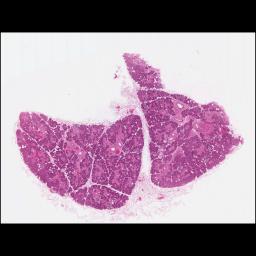

TL_153 Parotid

TL_155 Submandibular Gland

TL_158 Submandibular Gland